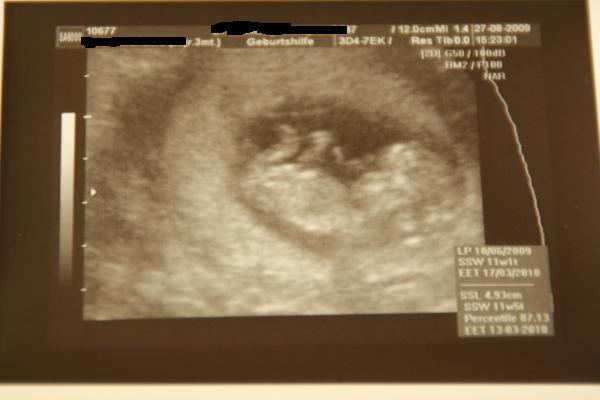

Hallo Mädels, komme gerade von der VU. Baby ist SSL 4,93 cm, es ist alles dran und zeitgerecht entwickelt, Nackenfalte ist auch perfekt und es hat uns gewunken (mein Freund war dabei). Haben sogar kurz das Herzchen hören dürfen und ich bin überglücklich. Hab heut auch schon ein 3D Bildchen bekommen, da zeigt es uns die Faust, fühlte sich wohl etwas gestört. Ach ja und er hat mich auf 11+5 vordatiert, heißt neuer ET 13.03.10, aber ich bleib erst mal beim 17.03., weil das kann sich ja nochmal ändern. lg Manu

Bild zu FA Bericht mit Foto - Forum für März - Mamis